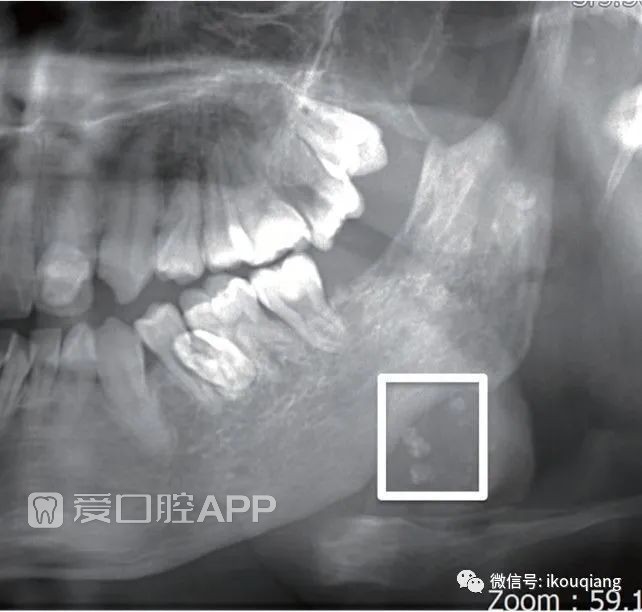

图15这张曲面断层片中可以看到,在下颌角区数枚钙化影像,中心密度稍低,似同心圆状。那么,这是什么呢?是发生在颌骨内的吗?是片子中的伪影还是提示某类疾病呢?

160011jynyzdclftbbkdii.jpeg

▲图15 曲面断层片中左下颌角区数枚钙化团块

这就是曲面断层片中的另一枚“彩蛋”——静脉石。静脉石:多见于静脉畸形(旧称面部海绵状血管瘤),其表现是在面颊部的无痛软性包块中,可触及豌豆大小、能活动的硬物。在X线片中可见大小不一的1至数个圆形钙化影,它是由于瘤体血窦内的血液长期旋流,使血液中的盐类物质沉积,并与瘤体内的脱落细胞凝结而成。曲面断层片中,静脉石常位于下颌角区,多发,形态为圆形或橄榄形,边缘光滑,内部呈同心圆样结构,形似“牛眼”或“环靶”。有时会与下颌升支重叠,造成下颌升支呈现稍高密度颗粒感(图16)。

160012bw7fcuwtt090cvuw.jpeg

▲图16 静脉石